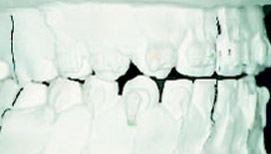

Эластопозиционеры эффективны и для коррекции окклюзии после предшествующего лечения другими методами: одночелюстными или двухчелюстными аппаратами или Quad-Helix. При расширении зубных рядов или сагиттальном перемещении нижней челюсти появляется вертикальная щель в области премоляров, а при устранении дистопии клыков – в области клыков. Созданный на Set-up желаемый вид окклюзии достигается в течение всего нескольких недель (рис.7-9).

Рис.7: Аномалия II класса, проведено предварительное лечение двухчелюстным аппаратом.

Рис.8: Set-up для достижения точной окклюзии.

Рис.9: Через 3 месяца после начала ношения аппарата.